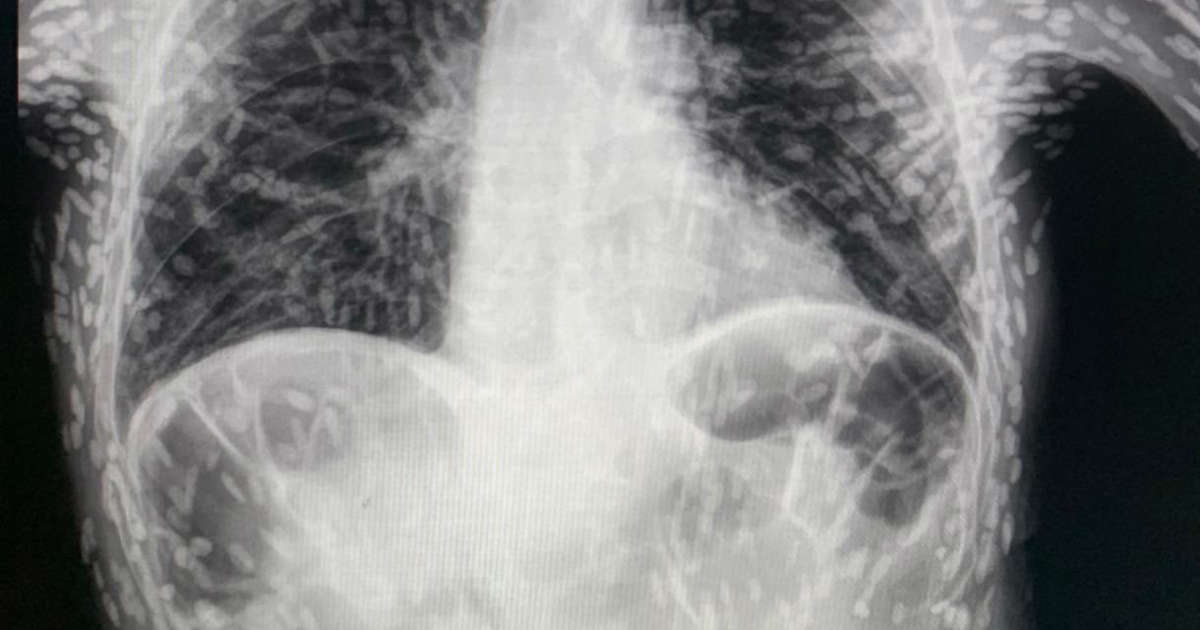

Man's cough turns out to be tapeworm infestation

A Brazilian man who went to the hospital with a cough was found to have tapeworm larvae in his body. The condition, called cysticercosis, is caused by ingesting tapeworm eggs, often found in undercooked pork. While usually harmless, the larvae can cause health problems if they travel to other parts of the body, such as the brain. The Taenia solium, or pork tapeworm, is responsible for 30% of epilepsy cases in endemic regions. Poverty and lack of access to medication often lead to poor treatment of the condition.